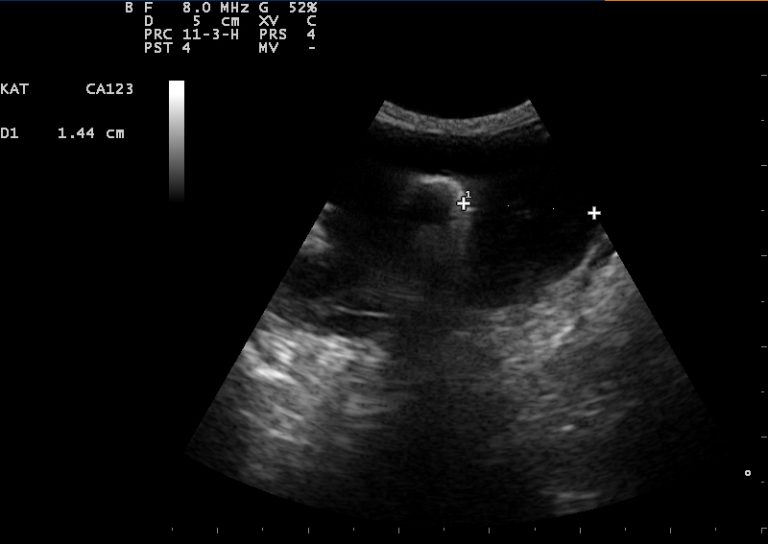

Echografie

Behalve voor drachtecho’s, waarbij we kijken naar het aantal pups bij een drachtige hond, kat, konijn, cavia of fret, wordt het echografisch onderzoek nog voor veel andere onderzoeken gebruikt.

Om beter inzicht te krijgen wat er zich ín het dierenlichaam afspeelt, is het mogelijk om een echo te maken. Hiermee kunnen we verschillende organen goed in beeld krijgen.

Hoe gaat het echografisch onderzoek in zijn werk?

Als u een afspraak heeft voor een echo van uw huisdier, kunt u daar in de meeste gevallen bij zijn. Zeker bij honden helpt het als de eigenaar erbij blijft voor een vertrouwd gevoel. Ongeveer een uur voor een buikecho mag het dier niet plassen. Dit zorgt ervoor dat de blaas goed gevuld is, die zowel zelf goed bekeken kan worden, als een uitgangspunt vormt voor de oriëntatie in de buikholte. Afhankelijk van de indicatie voor de echo kan het zelfs nodig zijn om langer niet te laten plassen.

Tijdens de echo ligt uw huisdier op de rug op een kussen (voor een buikecho) of op de zijde op een speciale tafel (voor een hartecho). De buik of het gebied van het hart worden geschoren, waarna er speciale echo-gel op de buik of borst wordt aangebracht. Dit zorgt voor een direct contact van de echo-probe met de huid, zonder dat er hinderlijk lucht tussen zit, die het beeld kan verstoren.

Soms kan het tijdens een echo nodig zijn om bijvoorbeeld urine uit de blaas op te zuigen, of een afwijkende structuur aan te prikken. Afhankelijk van het karakter en de locatie van de afwijking, kan er een roesje nodig zijn. Houd daarom voor de zekerheid uw dier 12 uur nuchter vóór de echo.

Aan het eind van de echo-sessie legt de dierenarts uit wat hij heeft gezien en wat het plan gaat worden. Soms kan het nodig zijn verder onderzoek in te zetten, zoals een bloedonderzoek of röntgenfoto’s.